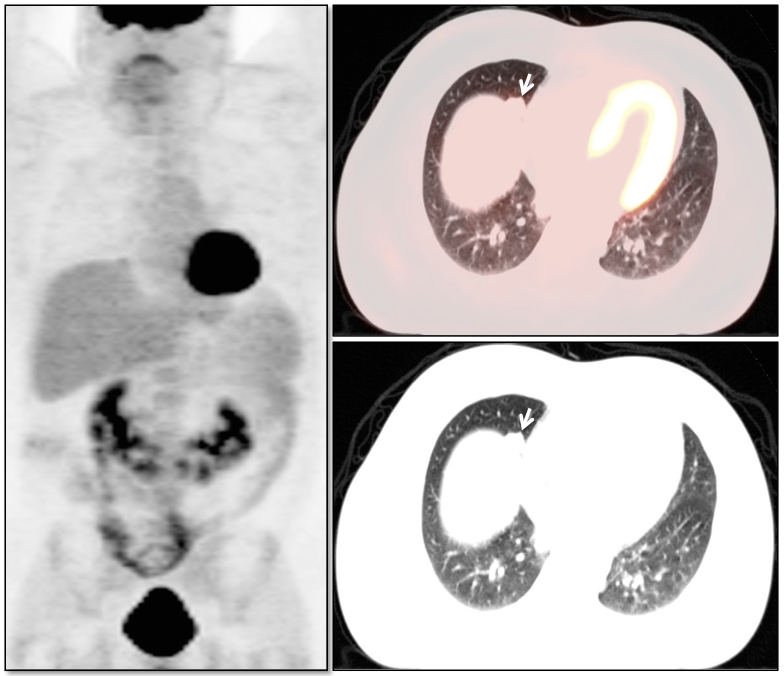

Lung Nodule Identification:

NAC images can occasionally be useful in identifying mild to moderately FDG-avid lung nodules, especially those located in the lung periphery or lung bases.